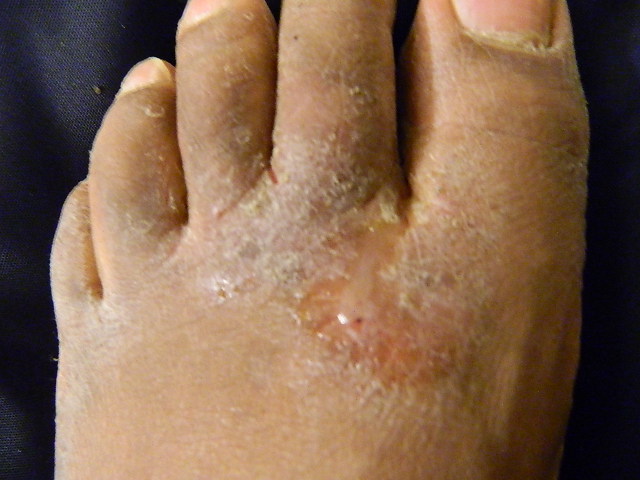

무좀은 피부사상균에 의해 발생하는 흔한 곰팡이 감염으로, 만성 사지간형, 족저형, 급성 궤양형, 수포성 등 다양한 증상으로 나타난다. 발가락 사이, 발바닥, 발 등에 주로 발생하며, 가려움, 발적, 궤양, 물집 등의 증상을 보인다. 무좀은 전염성이 강하며, 개인 위생 관리, 공공장소 위생 수칙 준수, 예방적 치료 등을 통해 예방할 수 있다. 치료에는 국소 항진균제, 경구 항진균제, 열 요법 등이 사용되며, 증상이 심하거나 재발하는 경우 경구 항진균제를 복용할 수 있다.

무좀은 만성사지간형, 족저형(만성 각질형, 모카신족), 급성 궤양형,[18] 수포성[9][11][12]의 네 가지 유형으로 나타난다. 사지간형은 발가락 사이, 족저형은 발바닥에 발생한다. 궤양성 질환은 각질성 가장자리가 있는 습윤된 병변을 포함한다.[18] 수포성 질환은 수포와 대수포(물집)가 특징이며, 이들은 체액이 차 있는 병변으로 크기에 따라 구분된다.[13]

무좀은 발가락 사이(사지간)에서 가장 자주 발생하며, 넷째와 다섯째 발가락(새끼발가락과 그 옆 발가락) 사이가 가장 흔하게 나타난다.[14][15][16] ''Trichophyton rubrum''에 의한 사지간 무좀은 증상이 없거나, 가려움증이 있거나, 발가락 사이 피부가 붉어지거나 궤양성(각질이 생기고, 비늘이 생기며, 피부가 젖은 상태로 유지되면 부드럽고 흰색임)[3][17]을 띨 수 있다. ''T. mentagrophytes''에 의한 사지간 무좀의 급성 궤양성 변이는 통증, 피부 습윤, 피부 침식 및 균열, 딱지, 그리고 이차적인 세균 감염으로 인한 악취가 특징이다.[12]2. 2. 족저형 (모카신형)